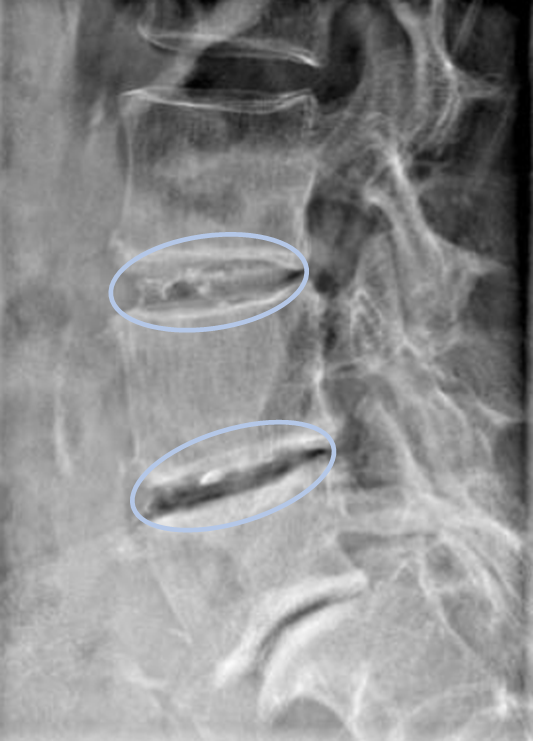

患者様と相談の元、L3/4,4/5にセルゲル法を施行

DiscoGelを入れた後の画像になります。